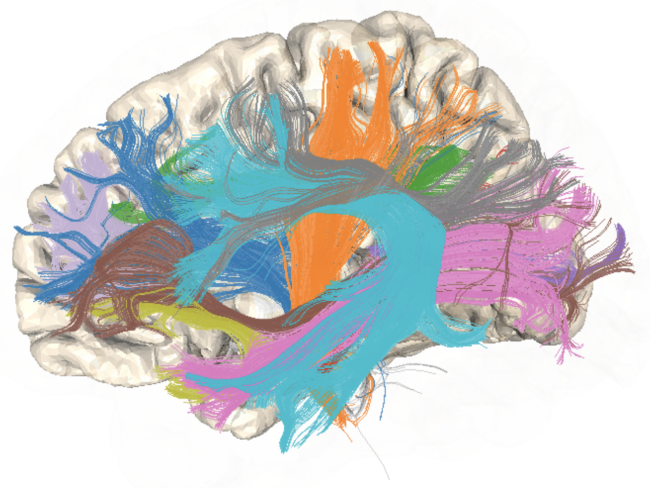

Diffusion Imaging

Tract Profile

AFQ-Browser

Yeatman, J. D., Richie-Halford, A., Smith, J. K., Keshavan, A., & Rokem, A. (2018). A browser-based tool for visualization and analysis of diffusion MRI data. Nature communications, 9(1), 940.